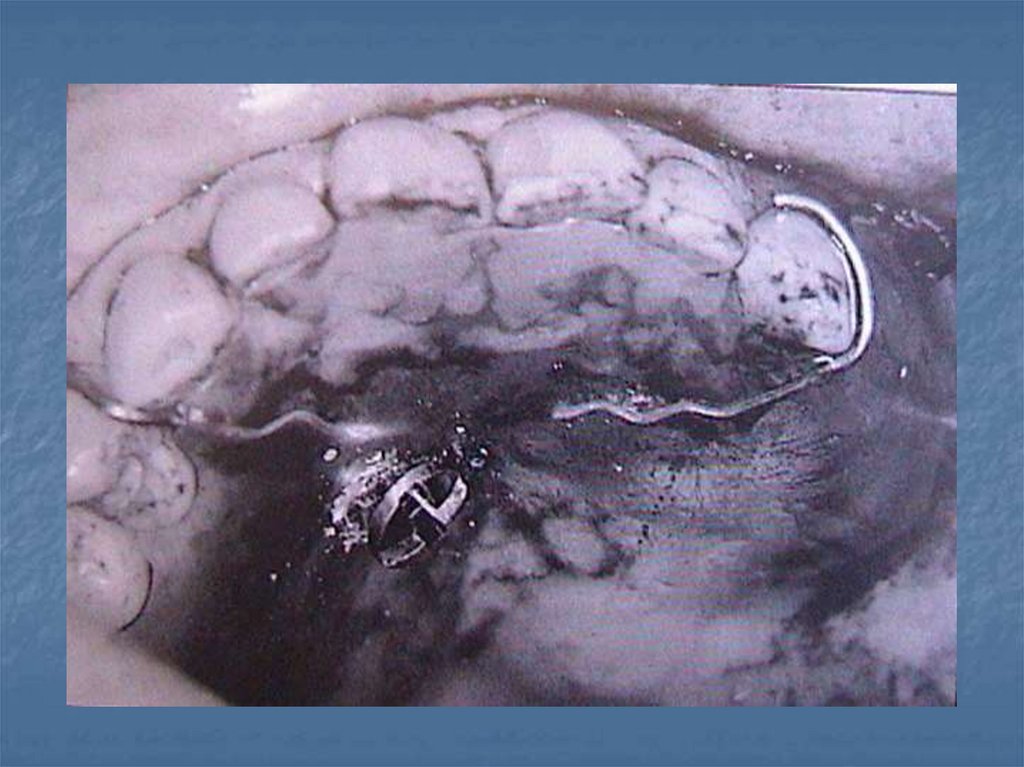

52. İmmediat obtüratörler

Ameliyattan önce ölçü alınır. Ameliyat

edilecek bölge model üzerinde tahmini

olarak kazınır. Protez hazırlanır. Ameliyatı

takib eden dakikalarda takılır kullanma

süresi 8-12 haftadır.